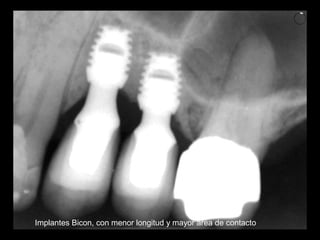

Implantes Bicon

Implantes Bicon, con menor longitud y mayor area de contacto

Implantes Bicon, conmenor longitud y mayor area de contacto